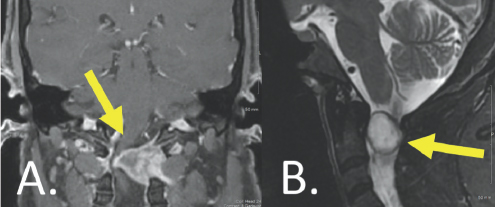

In the emergency department, MRI scans of Isabella’s brain and cervical spine were obtained. MRI of the cervical spine revealed a large tumor near the craniocervical junction resulting in severe impingement of her spinal cord (Figure 4.1). The source of her progressive neurologic disability had been identified. Based on its appearance on the MRI, the radiologist suspected the tumor was of peripheral nerve sheath origin

(Right) A large sized white blob is shown attached to a grey vertical column. A yellow arrow points to this white blob. Both structures are surrounded by other gray structures. (Right) A white spherical blob is highlighted by a yellow arrow. This blob is located in the center of the image overlapping a light gray colored column. These structures are surrounded by other gray and white structures.

FIGURE 4.1 Coronal, T1-weighted, post-contrast (A) and sagittal, T2-weighted (B) imaging demonstrated a large extramedullary tumor (yellow arrows), resulting in severe impingement of the high cervical spinal cord.